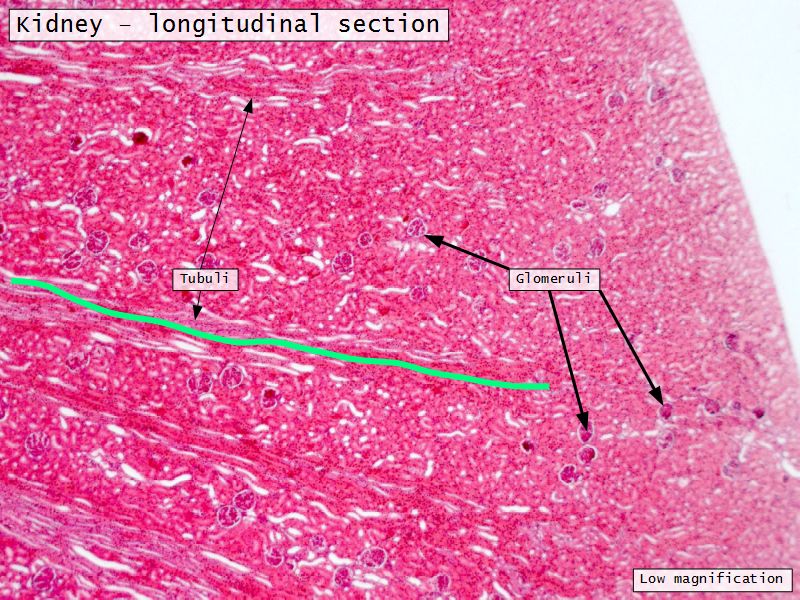

Appearance

- Cortex

- Renal corpuscles

- Convoluted tubules

- Medulla

- Loops of Henle

- Collecting tubules